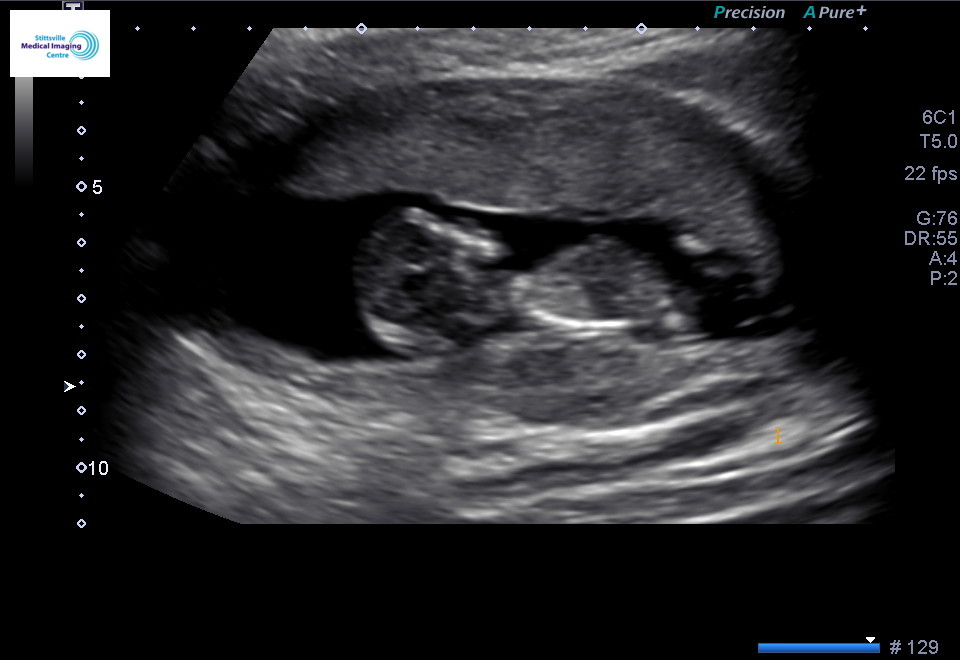

Week 10 exactly!! So cute! As soon as the doctor found the baby we saw the baby dancing and moving around! Super exciting! Due July 17,2019